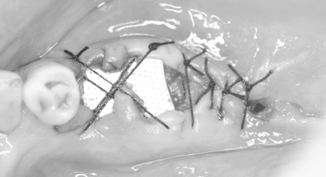

![]() |

骨の吸収が大きいため、骨造成(オープンバリアメンブレンテクニック)のみをおこない、期間をまってインプラント埋入しました。